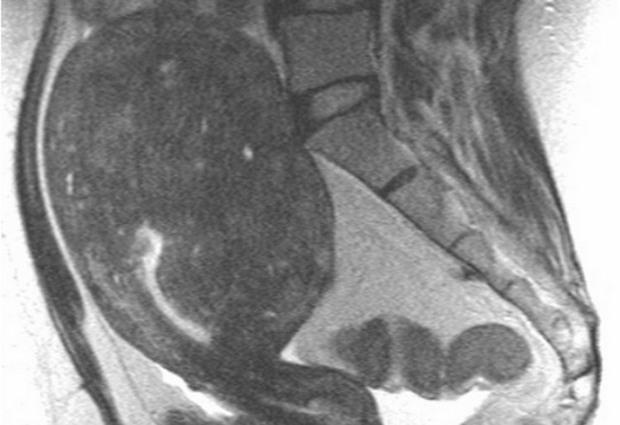

По-настоящему болезненным признается аденомиоз 3 степени. В этот период разросшаяся слизистая оболочка закрепляется в матке, врастая в нее. Возникающие кистообразные уплотнения продолжают функционировать как здоровая ткань, реагируя на приближение овуляции и менструации. Данное явление объясняет возникновение болевых симптомов в период всего цикла. Для четвертой стадии развития аденомиоза характерно прорастание эндометрия в органы брюшной полости.

Аденомиоз 1 степени – поражается подслизистый слой, аденомиоз 2 степени – очаги появляются в мышечном слое, аденомиоз 3 степени – клетки эндометрия проникают во всю толщину матки, аденомиоз 4 степени- процесс переходит на соседние органы (брюшина, кишечник).